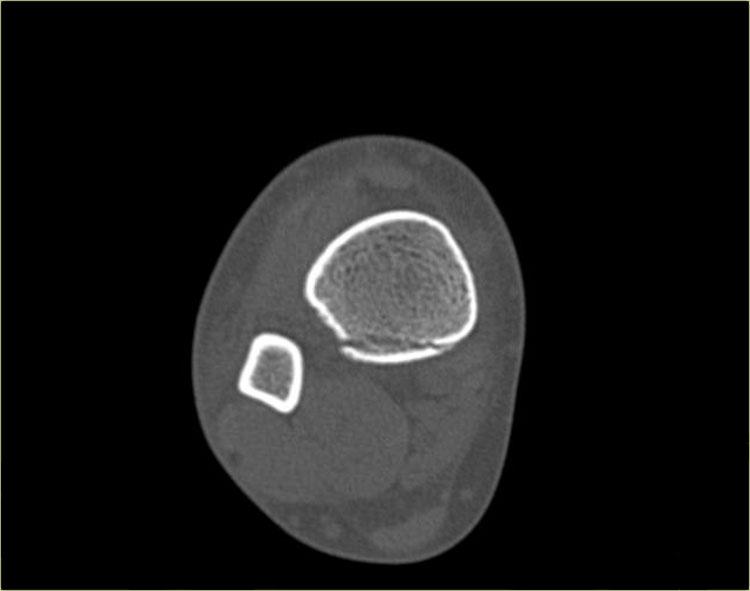

Hãy quan sát các hình ảnh và tiếp tục đọc phần bên dưới.

Thoạt nhìn, hình ảnh này có vẻ giống gãy xương Weber B với đường gãy chéo ở xương mác quan sát thấy trên tư thế chụp nghiêng (mũi tên đen).

Tuy nhiên, cần lưu ý rằng đường gãy này dừng lại ở mức sụn tiếp hợp.

Đây chính là đường gãy hành xương trên mặt phẳng trán.

Trên tư thế chụp thẳng (AP), có thể thấy một vùng thấu quang trong lòng đầu xương, tương ứng với đường gãy đầu xương trên mặt phẳng đứng dọc.

Cũng cần chú ý rằng sụn tiếp hợp phía trong đã đóng, trong khi phần ngoài vẫn còn mở (mũi tên xanh).

Chúng ta cần giả định rằng có hiện tượng tách sụn tiếp hợp (epiphysiolysis) ở phần ngoài này.

Đây là một ví dụ khác.

Mảnh gãy hành xương rất nhỏ, đây thường là trường hợp hay gặp (mũi tên đỏ).

Đường gãy qua đầu xương được chỉ thị bằng mũi tên xanh.